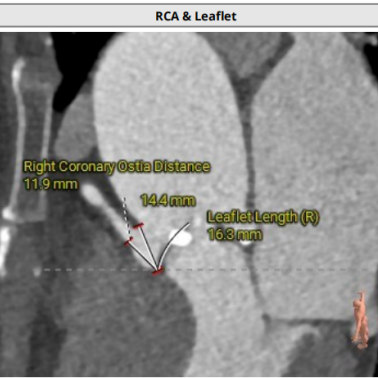

术前CT评估

● 左右冠脉开口高度尚可,切线位左右冠瓣叶长度>冠脉开口到瓣叶附着缘距离;

● 瓦氏窦、窦管交界内径正常,升主动脉扩张;